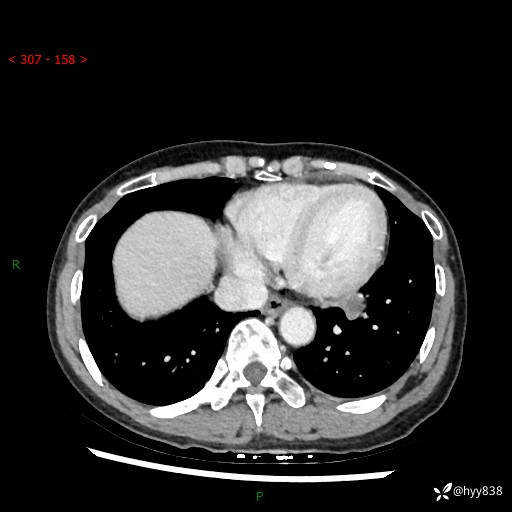

【检查】:胸部CT平扫+增强

各期CT值:40hu 57hu 49hu